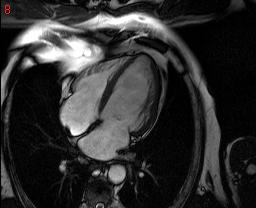

cardiac MRI Anonymous |

cardiac mri is some thing which can save many lives but the software available to analyse them are too costly...

the pictures show a few cardiac MRI data.. is there any way we can crop out hust the heart ,

itried a few thresholding scheles but, they dont seem to work very well

hey, the basic idea is to track the outer walls of the heart (the out line in red)

now as you can see this shows from a lot of views now we are more concerned with following the outer muscle of any one particular sequence.

now cardiac motion tracking is sold as S/W by loads oc companies but they cost a ton.

a cheaper way to track the cardiac motion will be welcome.